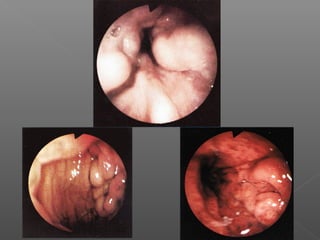

III. Métodos mecánicos

Hemoclips

Bandas elásticas

Endoloops

Suturas mecánicas

Hemocl

ips

Colocación de Hemoclips